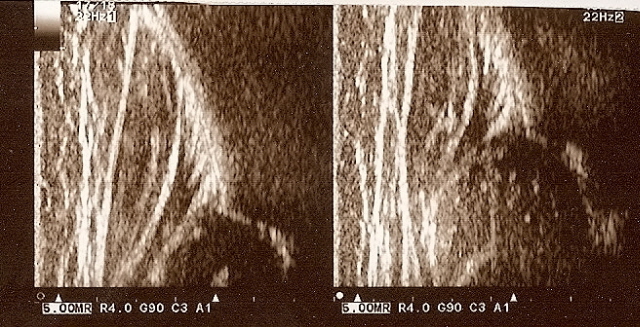

Type IIa+(GN coming to maturity) 6 weeks (below)

the bony roof satisfactory modeling

the bony rim angular but bony roof is only satisfactory ,the first part of bony roof is very good,but the second tail (deeper) is only satisfactory.

the cartilage roof cover the head;

the arrows show labrum (red) ;

the bony rim (yellow);

the lower iliac margin (blue) ,

the bony roof line (blue) is extends tangential to the lower iliac margin and tangent to the bony rim

the cartilage roof line(green) is drown tangential to the bony rim and through the middle point of the labrum echo;

asymmetry in the loose joint capsule; family DDH( when it occurs ask always about it)

the baseline (yellow) is drown parallel to ilium echo through the point of the junction of the perichondrium,the periosseum and ilium.

type I (abow) 6 weeks the bony roof is good

the bony rim blunt

the cartilage roof line(green) is drown tangential to the bony rim and through the middle point of the labrum echo ;

asymmetry in the loose joint capsule ,family DDH( when it occurs ask always about it)